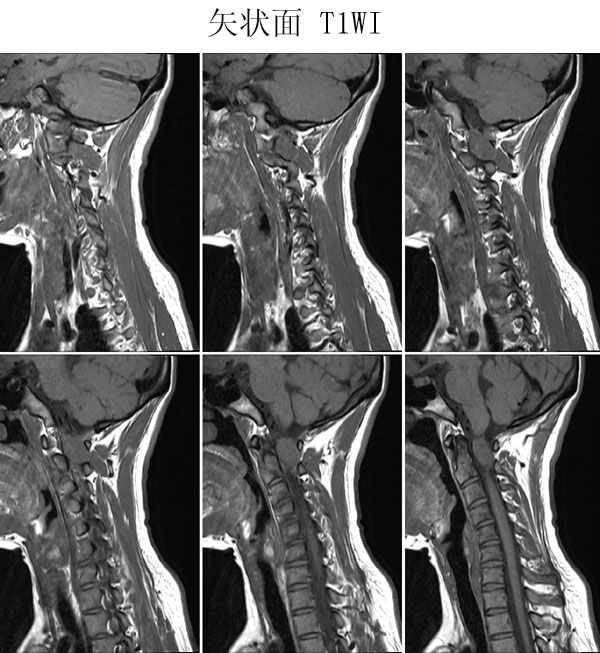

本病例来自广东同江医院

病史:女,27岁,洗头按摩时扭颈导致昏迷,检查发现颈椎占位

手术病理:

神经鞘瘤